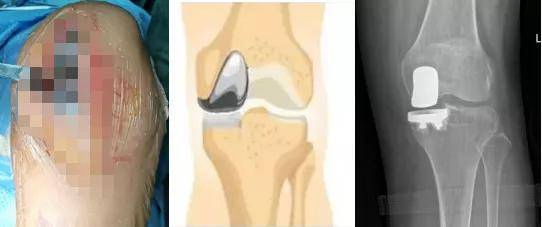

关节方面:髋、膝、肩、肘、踝等关节的人工关节置换手术;髋、膝关节置换术后的再次翻修术;肿瘤所致的髋、膝、骨盆等疾病的定制关节置换术等。

关节方向:各大关节的游离体摘除术,关节镜下半月板部分切除及镜下缝合术,关节镜下交叉韧带重建术,肩袖损伤修复术,关节软骨退变的镜下移植术。